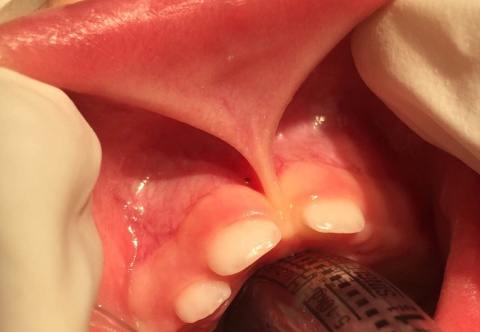

Type 1 Ankyloglossia

Type 2 Ankyloglossia

Type 3 Ankyloglossia